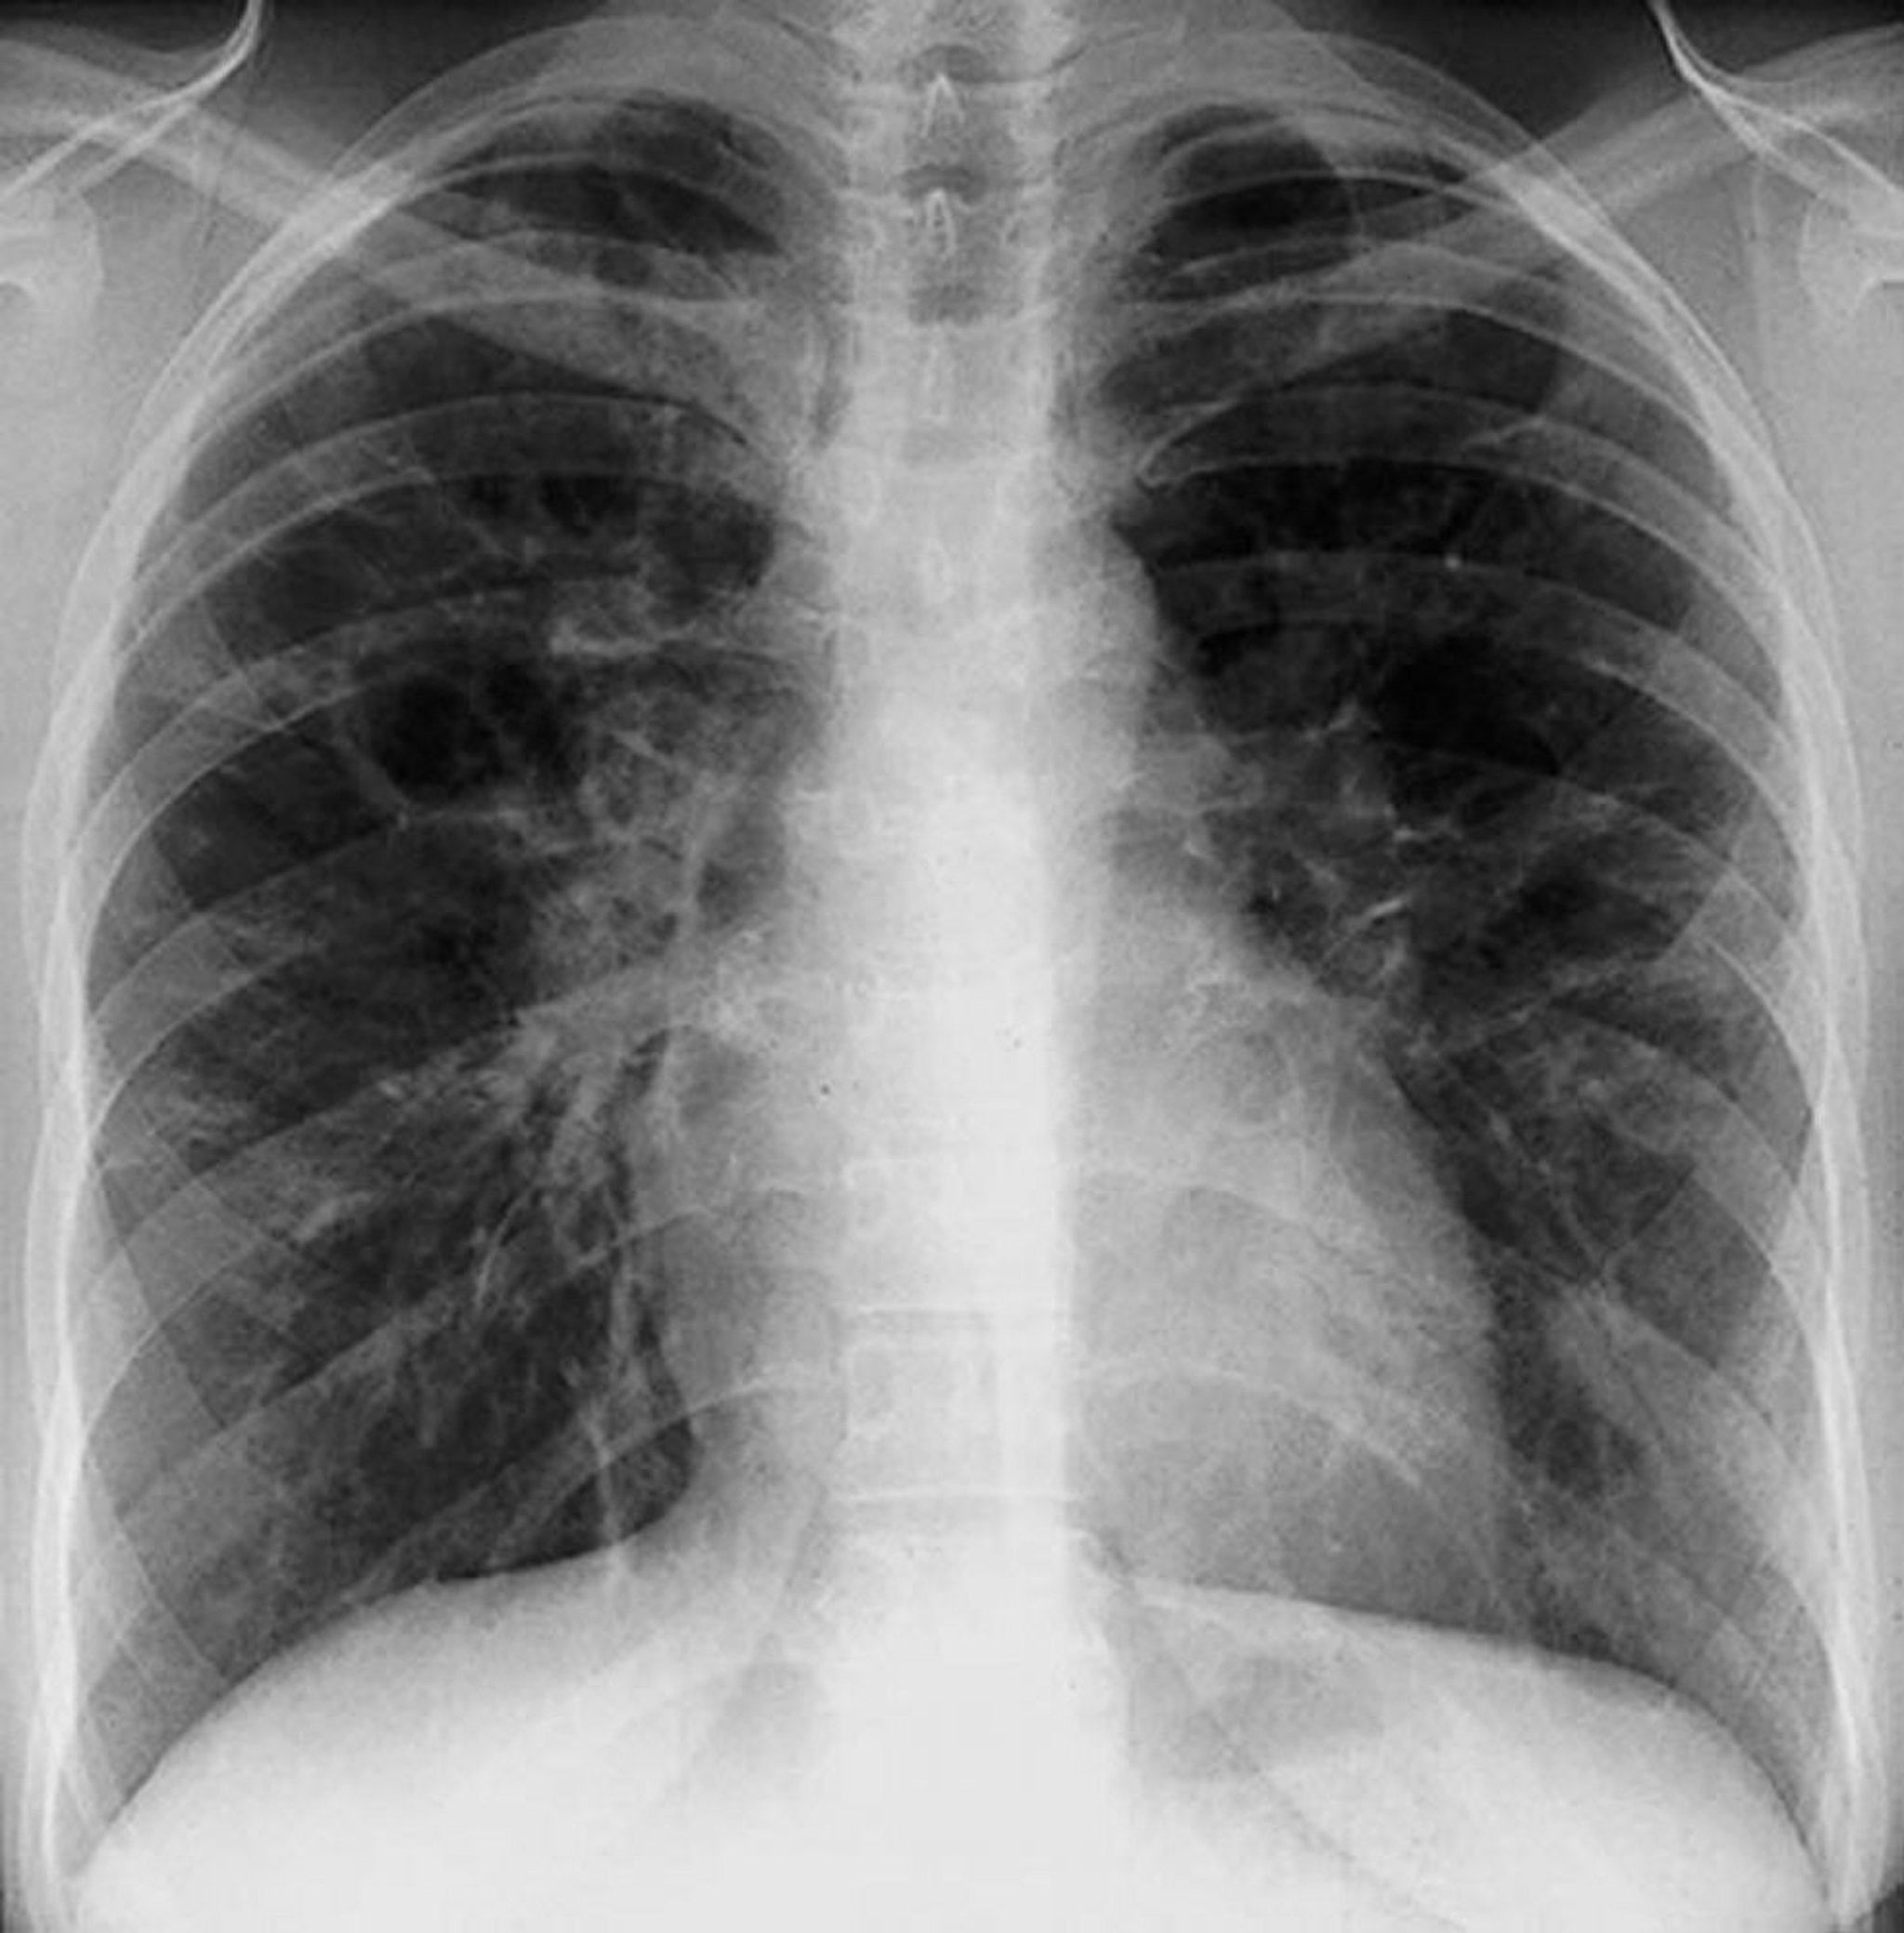

Саркоидоз — стадия III

Дифффузные интерстициальные помутнения без корневой лимфаденопатии при III стадии саркоидоза.

By permission of the publisher. Из Tanoue L, Elias J. In Bone's Atlas of Pulmonary and Critical Care Medicine. Edited by J Crapo. Philadelphia, Current Medicine, 2005.